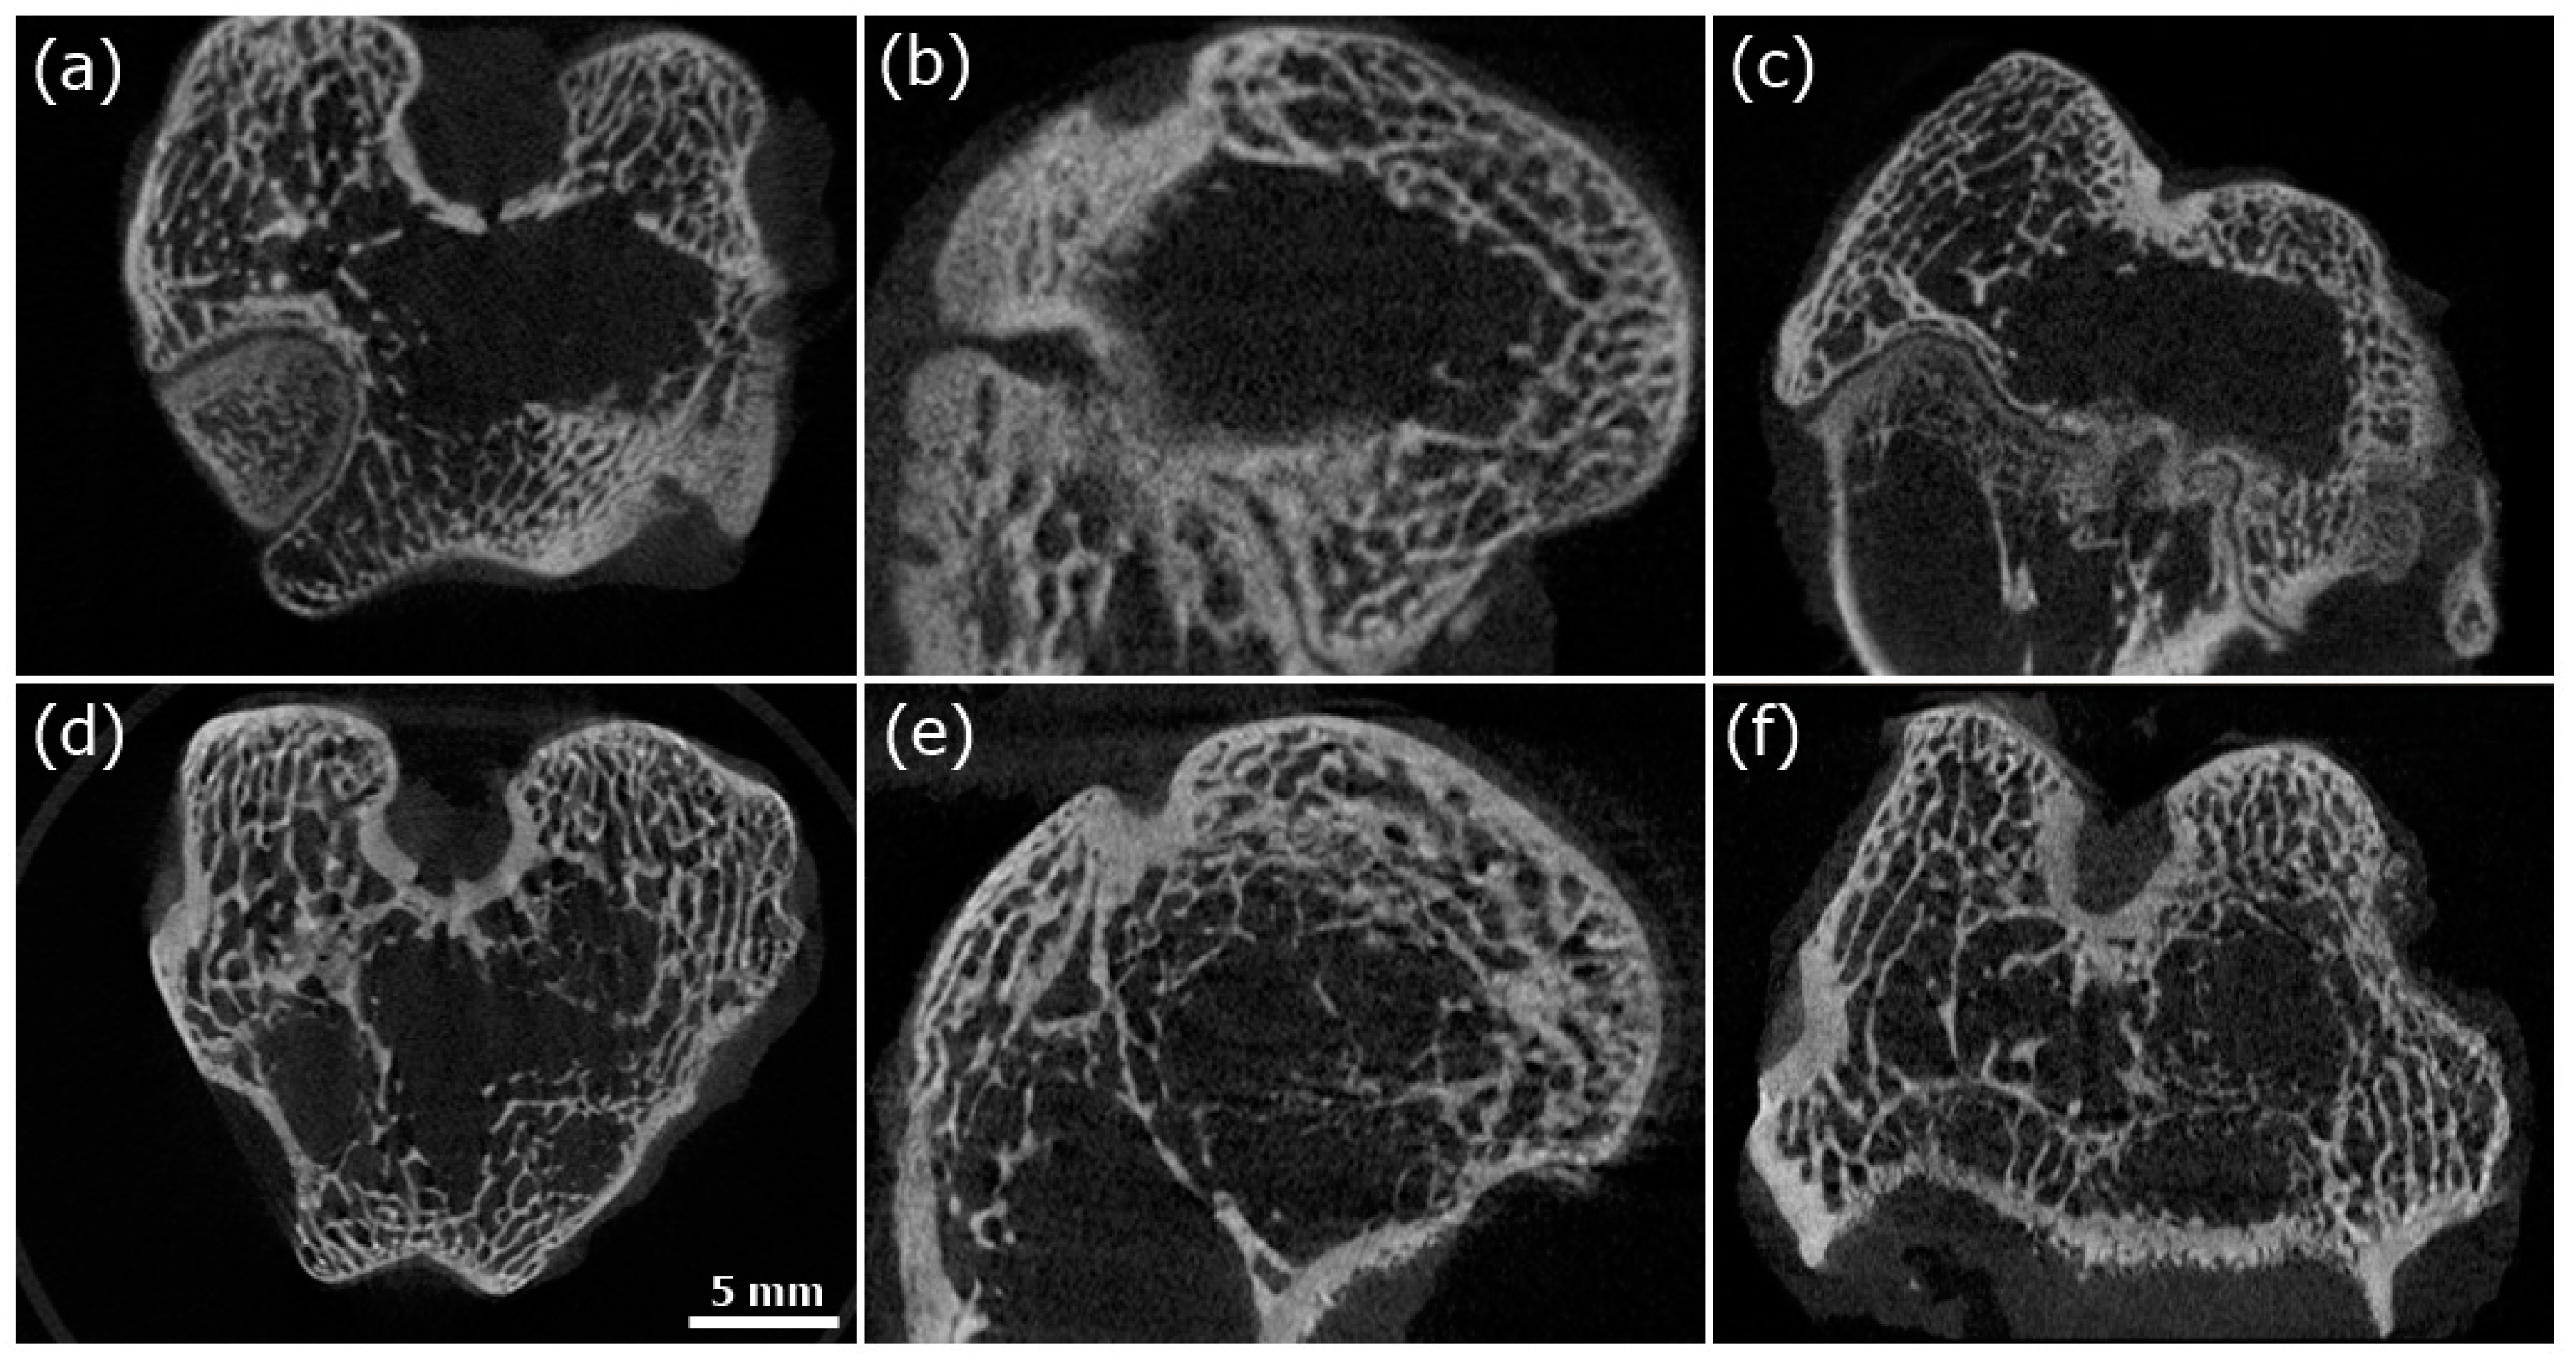

3.4. Microcomputed Tomography (Micro-CT) Evaluation

| BV/TV (%) | Tb.Th (mm) | Tb.Sp (mm) | |

|---|---|---|---|

| COL-HANF | 19.97 ± 3.50 | 0.260 ± 0.019 mm | 0.710 ± 0.173 |

| Control group | 16.59 ± 5.11 | 0.230 ± 0.005 | 0.548 ± 0.212 |